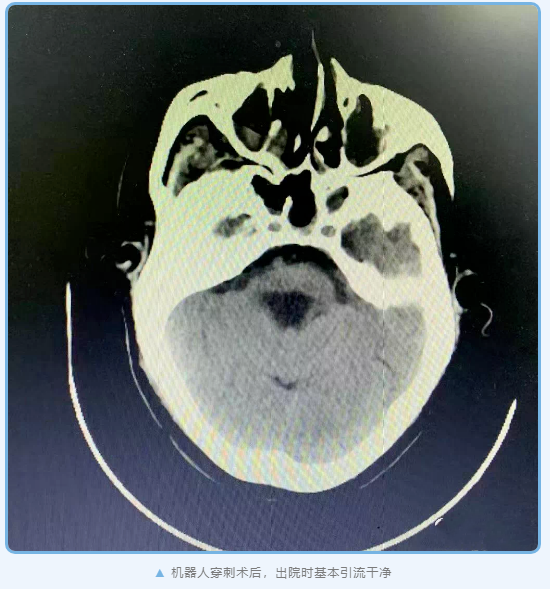

神经外科杨孔宾主任手术团队在全面评估后,诊断何叔为脑干出血。杨主任手术团队立刻通过机器人定向穿刺脑干血肿引流术,成功为何叔引流血肿。然而何叔脑部血肿虽已引流干净,生命体征也平稳, 脱离了呼吸机,但仍一直处于昏迷状态,经过3个月的各种其它康复促醒手段,仍未苏醒,被判定为植物状态。

众所周知,脑干出血病情凶险,在所有脑卒中疾病中病死率最高、预后最差。本例患者已经没有自主呼吸,采用机器人定向精准手术,效果良好、自主呼吸恢复。后续昏迷促醒采用先进的深度电刺激技术,术后还需要经过漫长、持续的催醒过程,期待患者苏醒的那一天早日到来。